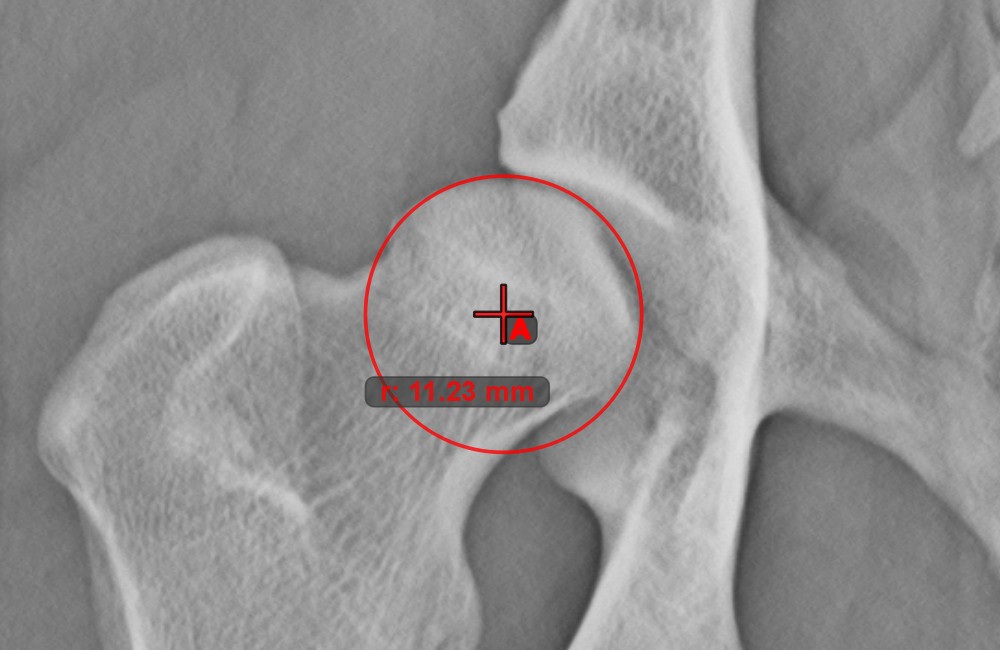

Circle from 3 Points

The Circle from 3 Points tool is a simple and effective way to create a circle from just three points.

Start by selecting the tool from the left toolbar and assign it to one of the available mouse buttons. Place the three points of the circle, or select the points from ones available on the scene. The circle will be automatically created based on the position of the three points. The origo of the circle will always be marked with O. The radius of the circle is automatically calculated.

Modify the position of the three points to change the radius of the circle by using the Select/Move Item tool.

../_images/image108.jpg